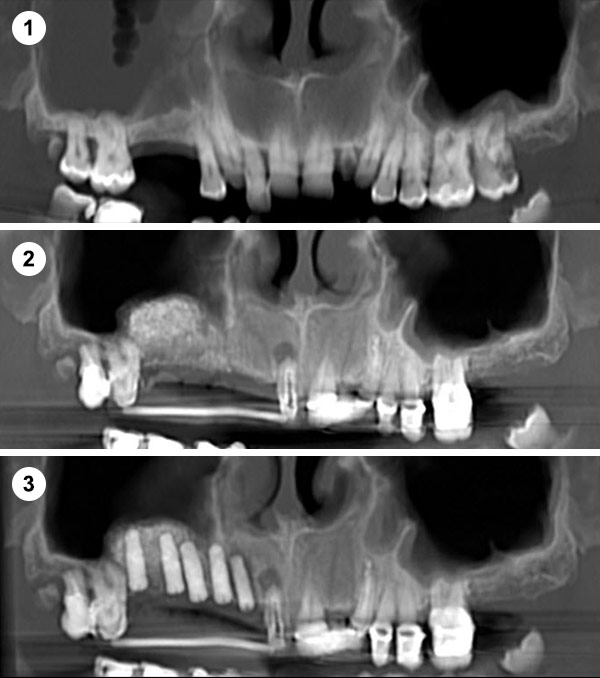

Esta técnica consiste en aumentar la altura y anchura del hueso en los maxilares introduciéndonos en el seno para conseguir una base ósea que permita la colocación de implantes.

Es un procedimiento sencillo que se realiza con anestesia local. Se practica una pequeña incisión a la altura de las raíces de los molares y premolares del maxilar superior, se crea una ventana en el hueso para acceder a la cavidad sinusal y se eleva la membrana para colocar un injerto de hueso en el suelo del seno maxilar.

Cuando no hay hueso ni distancia suficiente entre el maxilar superior y el seno (altura menor a 5 mm) que imposibilita la colocación de implantes.

Se realiza a través de una apertura lateral en la pared del seno maxilar (ventana lateral). Este enfoque permite un acceso directo a la membrana sinusal para su elevación.

Indicaciones: Se emplea en casos donde la cantidad de hueso residual es muy escasa (<5 mm) o cuando se necesita un aumento significativo del volumen óseo.